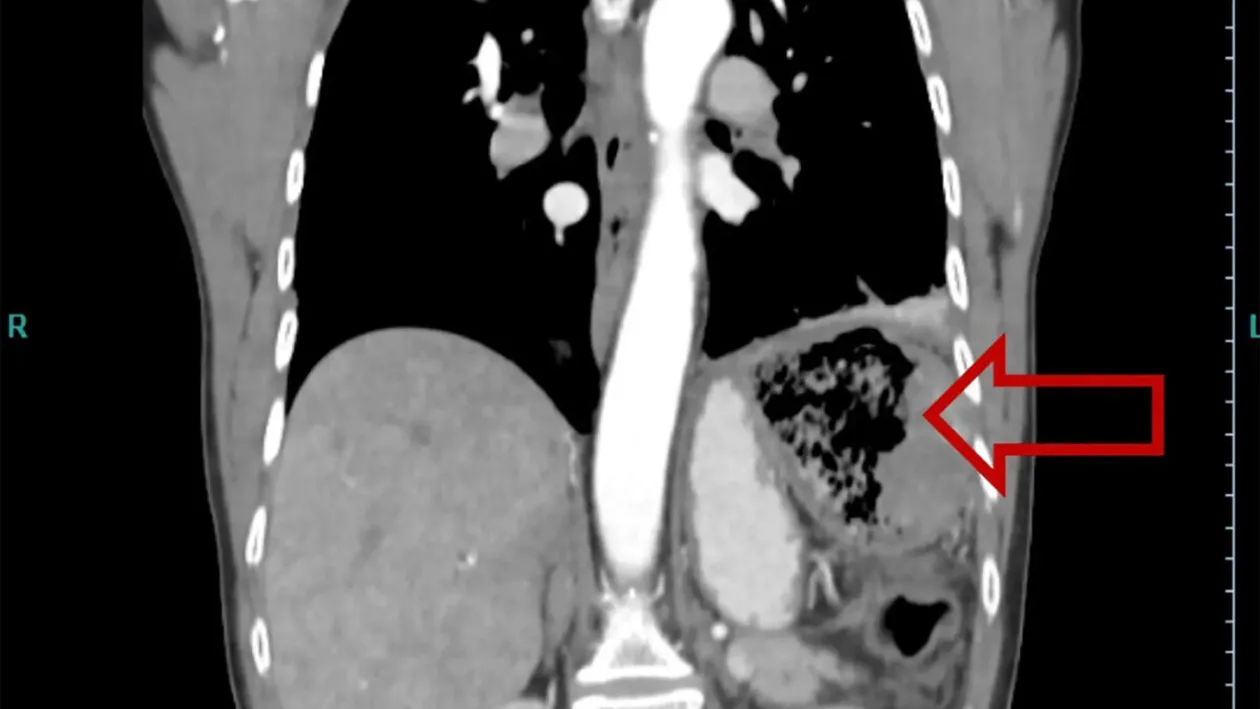

După ce s-a vindecat de cancer, la 20 de ani de la momentul intervenției chirurgicale, a început să aibă dureri abdominale severe, febră, transpira pe timpul nopții. S-a confruntat cu anorexie și slăbise excesiv. Femeia, fiind alarmată de aceste lucruri, a mers la spital. A făcut și o radiografie în urma căreia s-a descoperit că avea în partea stângă a intestinului un obiect. Era, de fapt, bucata de cârpă lăsată de medicul care a operat-o în anul 1999.

A intrat în operație, iar medicii i-au îndepărtat obiectul rămas în intestin. Nu este prima oară când se întâmplă astfel de greșeli medicale, arată nypost.com.